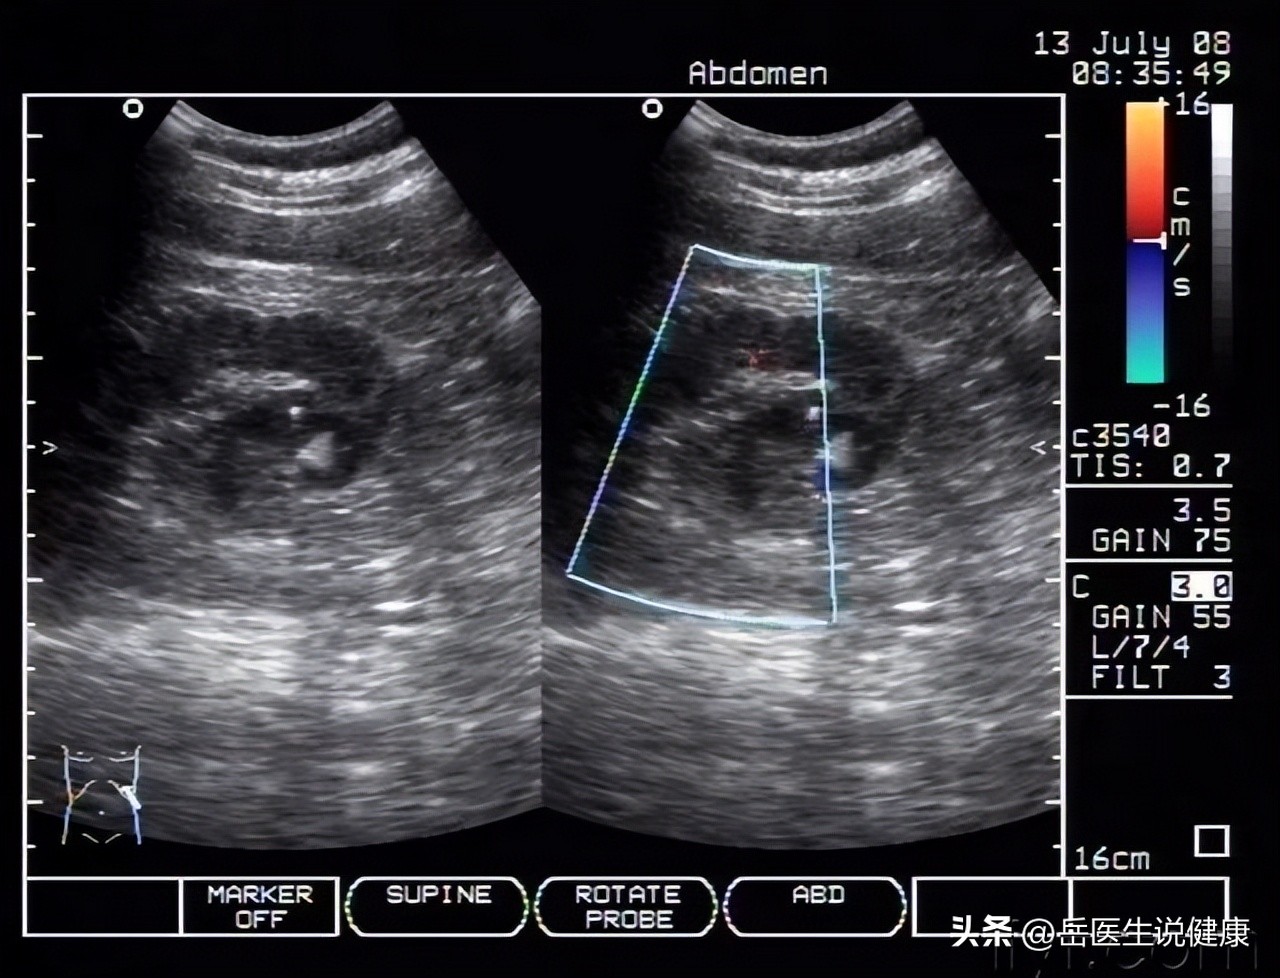

根据检查报告显示,王女士的白细胞和中性粒细胞数值升高,提示有感染征象,尿常规显示白细胞尿,尿培养也呈现阳性,肾脏超声显示肾盂黏膜出现水肿以及轻度的肾积水。

根据王女士的临床症状以及辅助检查,医生诊断为尿路感染中的急性肾盂肾炎。